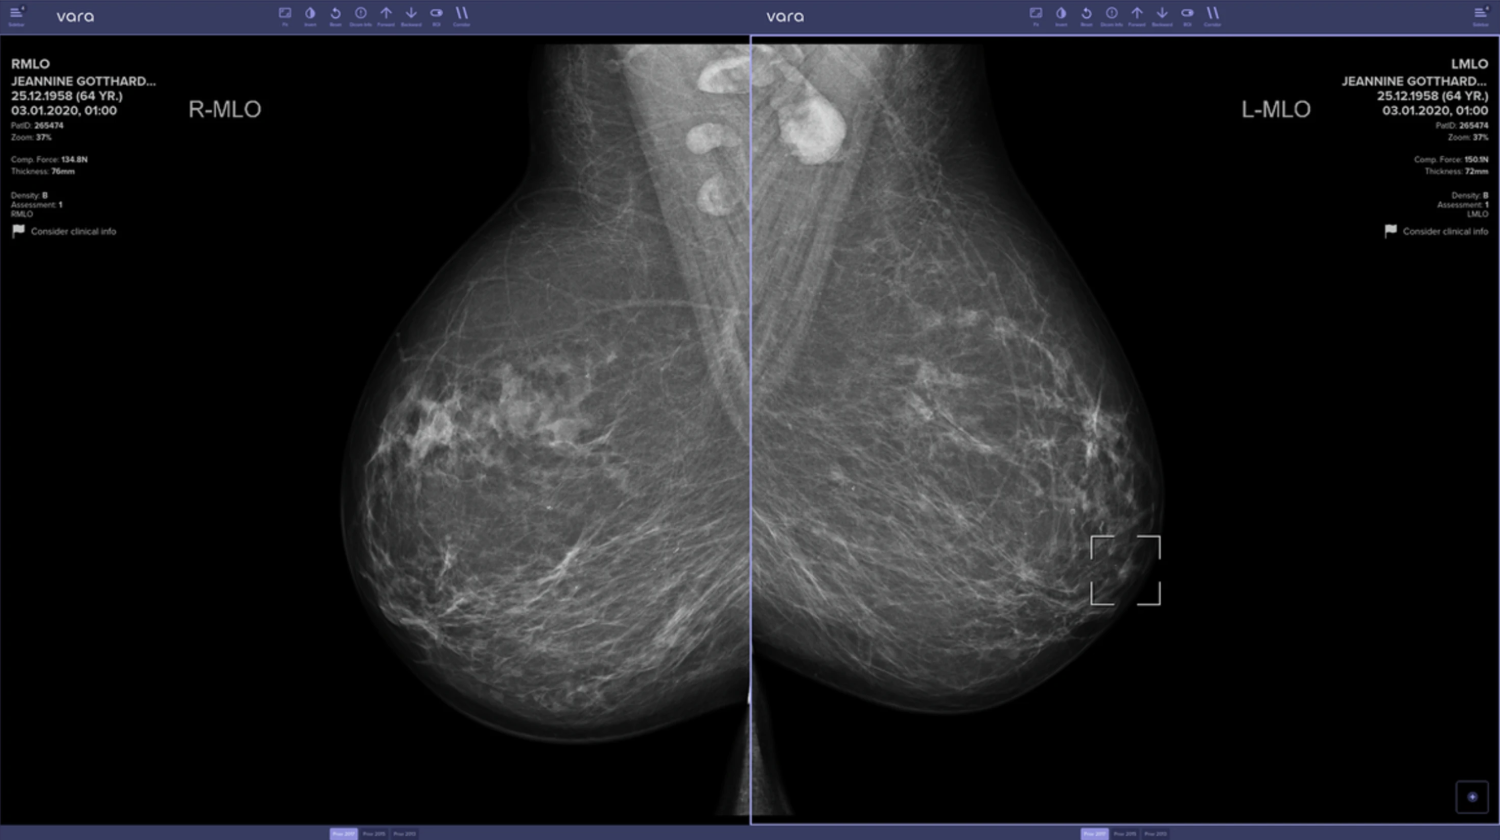

Исследование показало эффективность ИИ в обнаружении рака груди

Масштабное исследование в Германии подтвердило преимущества использования искусственного интеллекта при скрининге рака молочной железы. Исследователи проанализировали данные 461 818 женщин, часть из которых проходила обследование с применением ИИ, а часть — по стандартной методике с двумя радиологами.

В группе с ИИ выявляемость оказалась на 17.6% выше — 6.70 случаев на 1000 обследований против 5.70 при стандартном подходе. Важно, что количество ложных срабатываний осталось на том же уровне. Система не только помечает «нормальные» снимки, но и выдает предупреждения, если радиолог пропускает подозрительный участок: благодаря этой функции было выявлено 204 случая рака.

Особенно актуально это для стран вроде Великобритании, где наблюдается 29%-й дефицит радиологов. Правда, эксперты отмечают необходимость долгосрочных исследований: увеличение выявляемости медленно растущих форм рака может привести к избыточной диагностике.